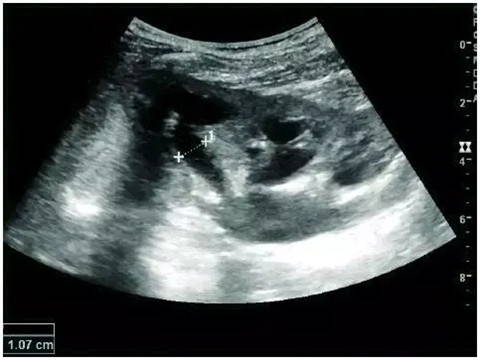

Features of complex renal cysts: septation, calcification, and irregular thickening of the cyst wall. Doppler ultrasonography is feasible for further evaluation. Bosniak grading and follow-up of complex renal cysts can be performed with contrast-enhanced ultrasonography or enhanced CT. The Bosniak classification can be divided into grades I-IV, grade I: simple cyst, grade IV: cystic malignancy risk 85%–100%.

Adult complex renal cyst with wall thickening in the lower pole, +, dashed distance: kidney length and complex cyst